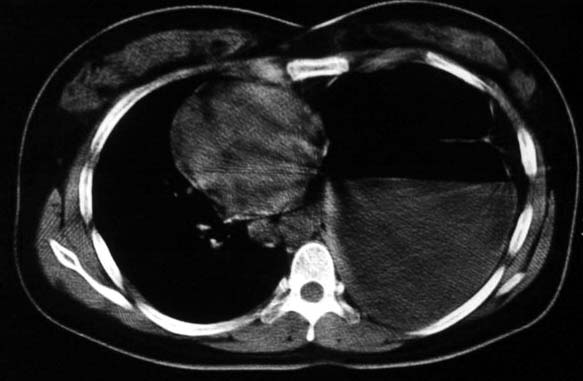

标题: CT5517:女性、24岁,反复胸痛、气促不能平卧半月。 [打印本页]

标题: CT5517:女性、24岁,反复胸痛、气促不能平卧半月。

支持膈疝,纵隔窗内可见消化道的内容物。

“反复胸痛、气促不能平卧半月”。+影像学表现=膈疝

谨慎!喝钡透视一下吧。冒然报一液气胸,临床再穿刺引流结果把胃戳个大洞就麻烦了!

不排除先天畸形,1.左肺支气管肺囊肿,左肺发育不良,2.左纵隔先天畸形?3.胸腔胃?